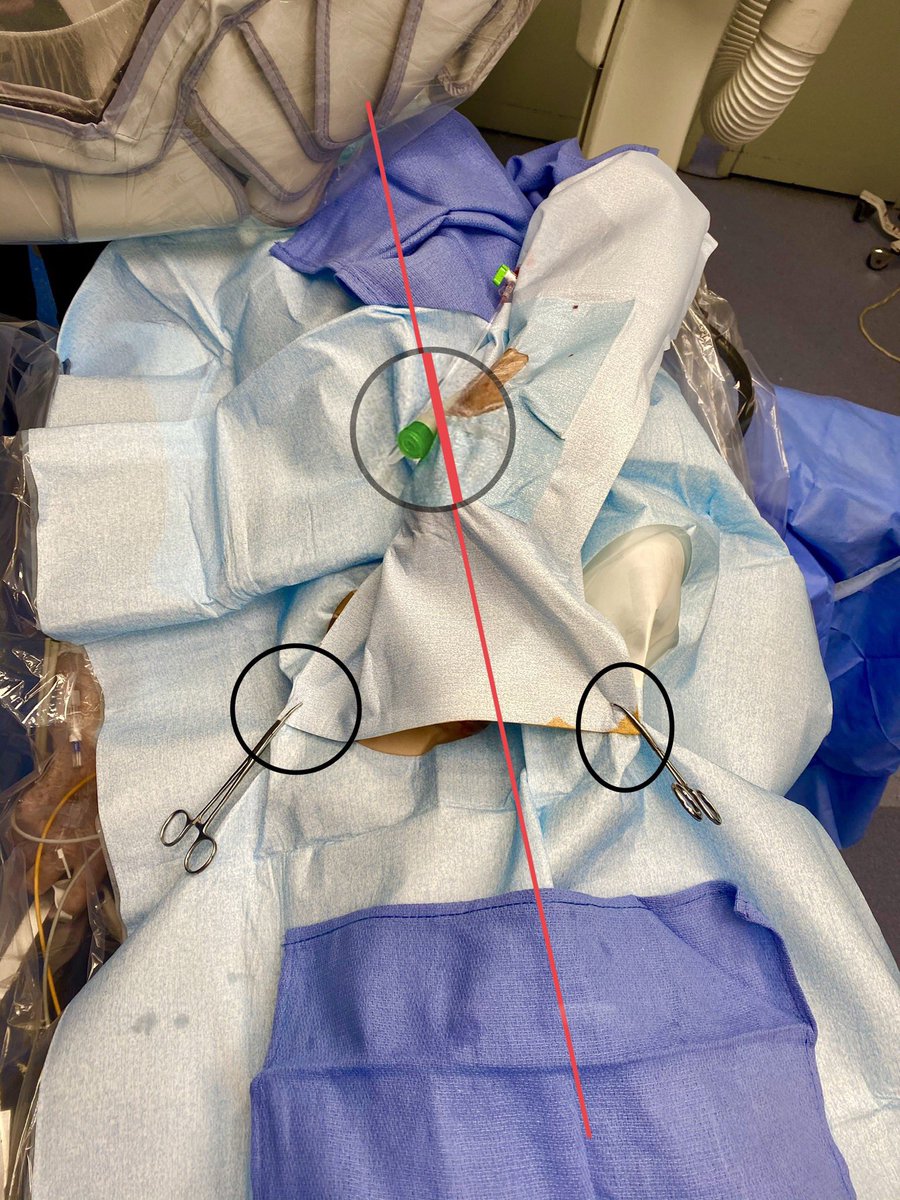

Ok, if we now have the BATMAN (Balloon-Assisted Translocation of the Anterior Mitral Valve) and ROBIN (Retrograde Radiofrequency Balloon-Assisted Optimization of Neo-LVOT) techniques, I’ll raise the stakes with: